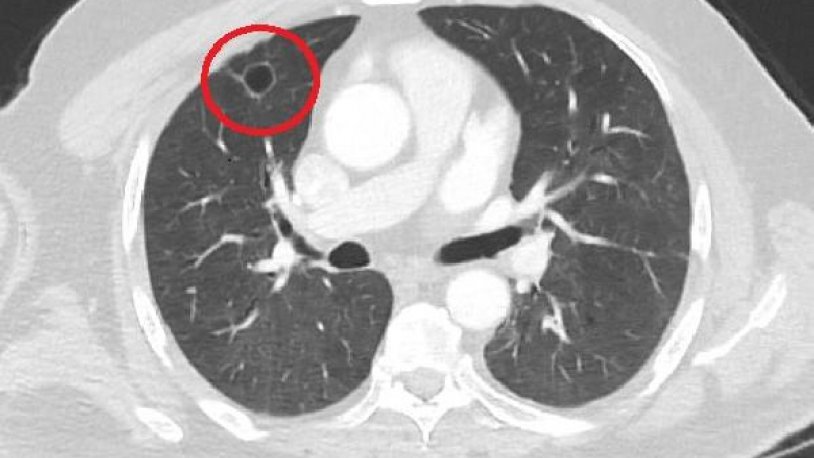

Dünya tıp literatüründe bir ilk! Türkiye'de tespit edildi